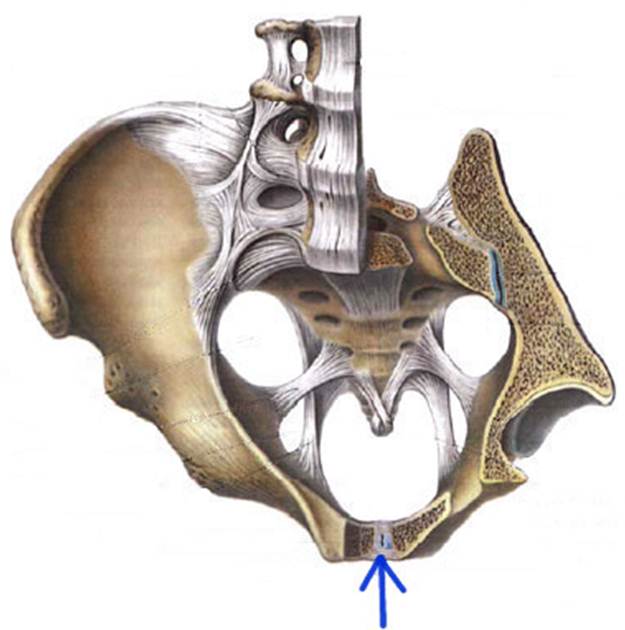

S: Стрелка указывает на Conjugata vera

S: Стрелка указывает на Conjugata diagonalis

S: Стрелка указывает на лобковый симфиз (русский язык).

S: Стрелка указывает на lig. Sacrococcygeum anterius